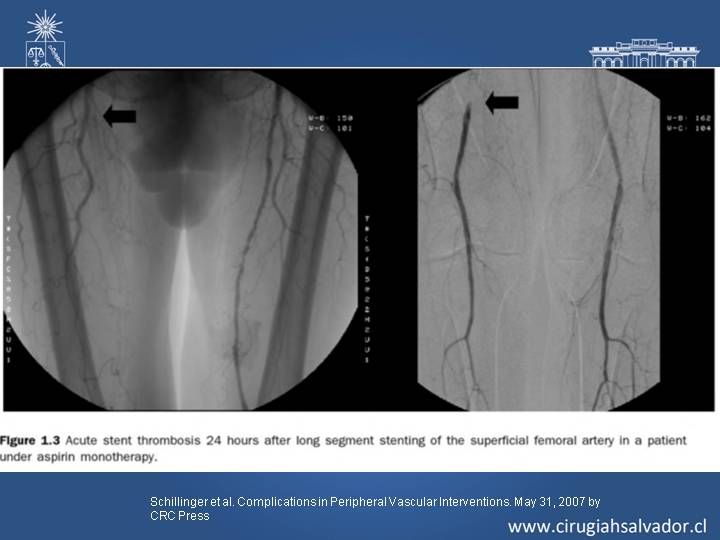

Complicaciones en Cirugía Endovascular

Vascular

| Autor: Dr. Roberto Macchiavello